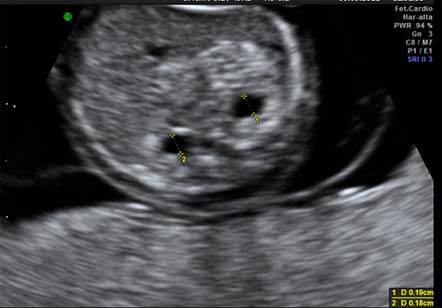

Ecografías que detectan el síndrome de Down

Pielectasia bilateral

Se observan las dos pelvis renales dilatadas y es un marcador de cromosomopatías.